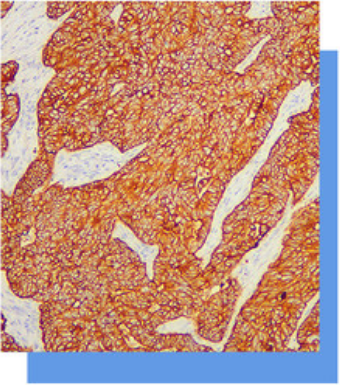

细胞角蛋白18 (CK18)分子量为45kDa,属

于低分子量A型细胞角蛋白,主要标记各种单层.上

皮和腺上皮,而复层鳞状上皮常为阴性,主要用于

腺癌的诊断。